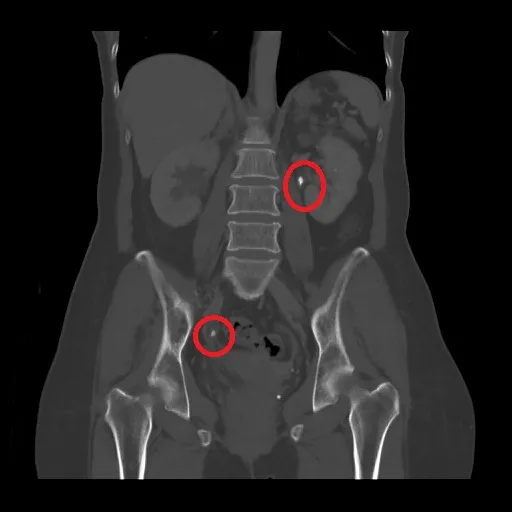

但此次婦人疼痛程度超過以往,直說「比生孩子還痛」,初步檢查,果然發現右側輸尿管及左側腎盂各有1顆1.5公分、1公分大的結石,已經出現腎臟發炎、多日高燒不退等症狀,醫療團隊先藉由經皮穿腎引流導管,抽出200多c.c.膿液,才稍稍舒緩疼痛感,但患者想到得再等2個星期才能取出結石,讓她心情跌落谷底,頻頻詢問是否有折衷方案。

醫療團隊經評估患者狀況後,決定採用超細軟式輸尿管鏡取石,過程中,將約1公尺長的細條狀軟鏡從尿道進入,經由膀胱、輸尿管一直到腎臟,將沿途發現的2顆結石,利用高功率鈥雷射擊碎粉塵化,之後再以吸出及自然排出方式完成碎石任務,術後結果讓患者十分滿意。